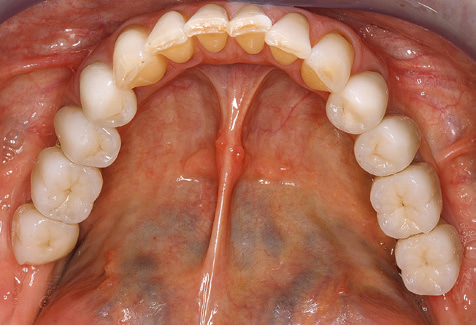

Eine 52-jährige Patientin stellte sich nach Zahnverlust im 3. Quadranten erstmals 2004 vor. Sie hatte den Wunsch nach einer prothetischen Neuversorgung. Im Rahmen der parodontologischen und radiologischen Diagnostik zeigte sich ein ausgeprägter parodontologischer Behandlungsbedarf. Die Zähne 48, 28, 27 zeigten zudem eine infauste Prognose und wurden entfernt (Abb. 1). Nach der erfolgreich abgeschlossenen systematischen PARTherapie wurde eine festsitzende implantatprothetische Versorgung mit Insertion von fünf Implantaten in Regio 35, 36, 37 und 46, 47 durchgeführt. Die prothetische Versorgung der natürlichen Zähne erfolgte mit verblendeten Zirkonoxidkeramikkronen, die Implantate wurden mit zweiteiligen individuellen Zirkonoxidabutments und ebenfalls verblendeten Kronen aus einer Zirkonoxidkeramik versorgt (Cercon base colored, Dentsply Sirona Lab). Die definitive Insertion der prothetischen Versorgung erfolgte im Jahr 2005.

Aufgrund der bestehenden parodontalen Vorerkrankung erfolgte die unterstützende Parodontaltherapie (UPT) in den ersten Jahren in einem DreiMonatsIntervall. Dabei zeigte die Patientin eine hohe Motivation und gute Compliance. Bei den jährlich erhobenen Sondierungsbefunden zeigten sich stabile parodontale Verhältnisse mit einem BOPIndex unter fünf Prozent. Aufgrund der stabilen parodontalen Situation und der guten Mitarbeit der Patientin wurde ab dem sechsten Jahr der prothetischen Funktionsphase das Recallintervall auf halbjährlich umgestellt. Auch mit diesem veränderten Recallintervall zeigten sich bei der jeweils jährlichen Aufnahme des Parodontalstatus stabile parodontale Verhältnisse, ohne Zunahme der Sondierungstiefen und einem BOPIndex unter fünf Prozent (Abb. 2a und b).

Im Rahmen der ZehnJahresKontrolle zeigten sich keine Hinweise auf einen fortschreitenden parodontalen Attachmentverlust oder einen periimplantären Knochenverlust (Abb. 3).

Die Patientin befindet sich weiterhin in einem halbjährlichen Intervall für die UIT. Nachfolgend werden am Beispiel dieser Patientin die einzelnen Arbeitsschritte einer strukturierten UPTSitzung aufgezeigt, so wie sie nahezu unverändert über den gesamten Funktionszeitraum von immerhin zwölf Jahren durchgeführt wurden. Natürlich wurden über diesen Zeitraum einige neue Materialien und Geräte in das Konzept integriert. In diesem klinischen Fallbericht wird das aktuelle Material und Gerätekonzept präsentiert.